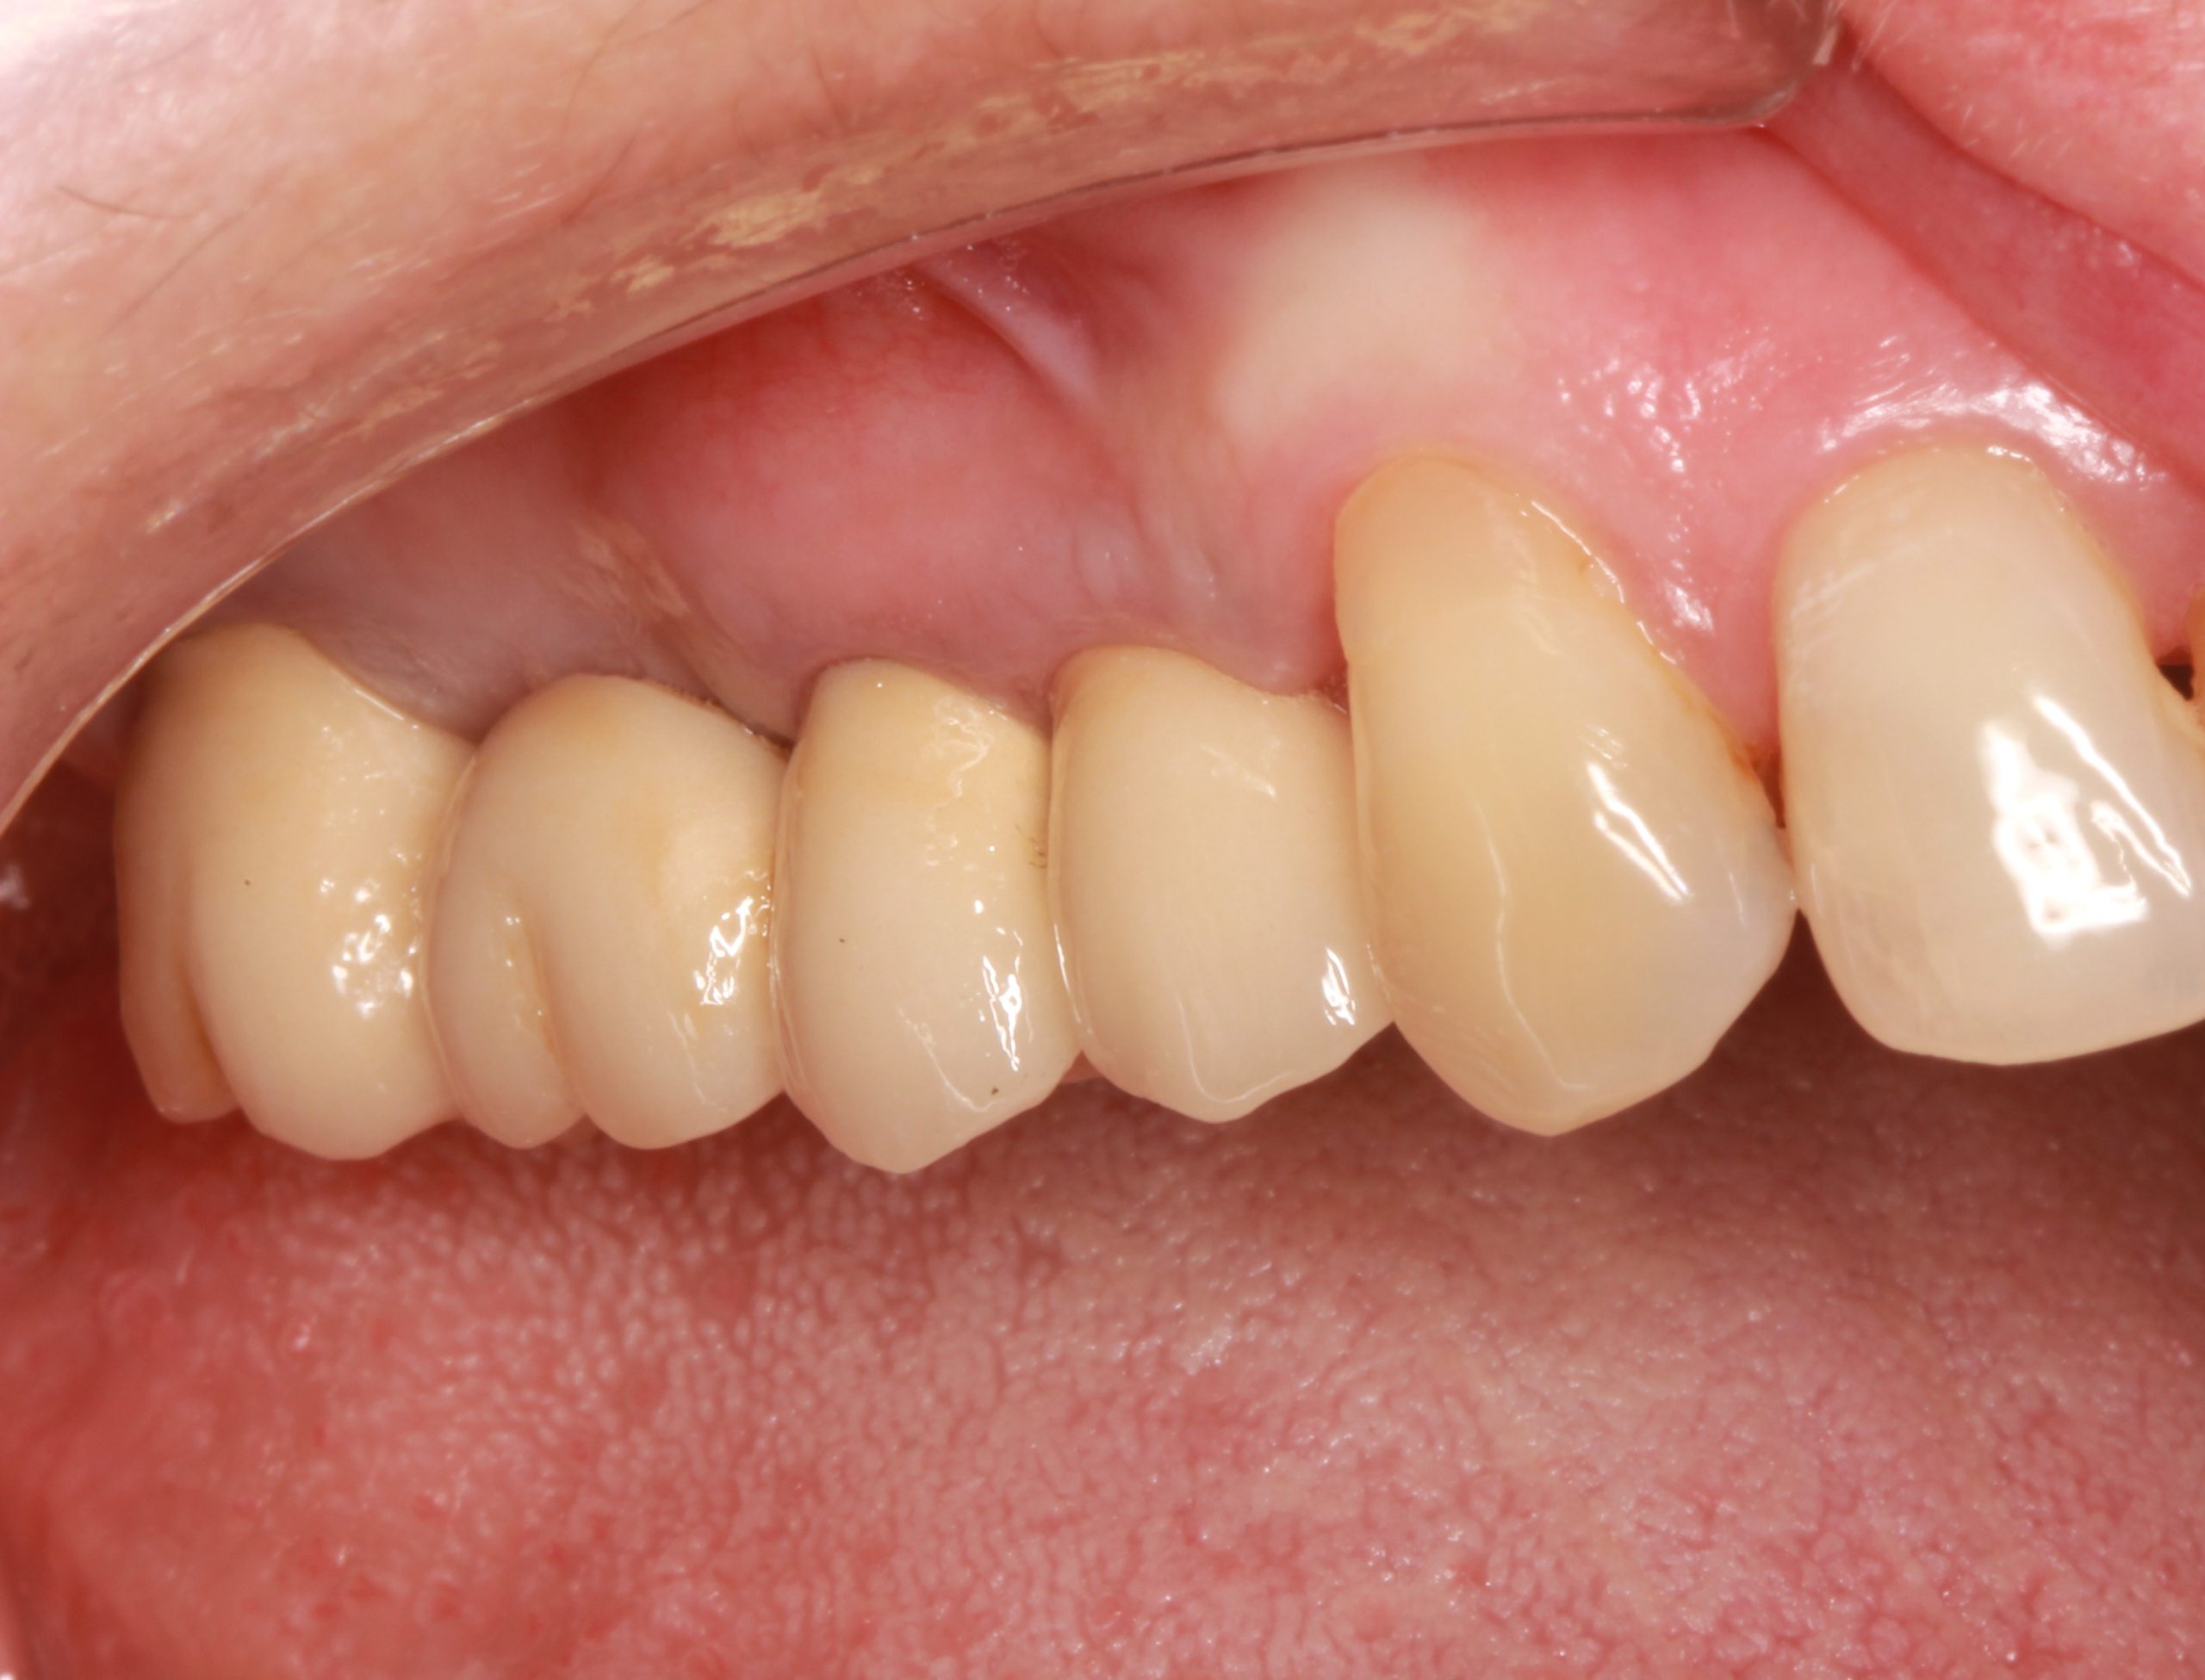

The final result after placing a fixed dental bridge on teeth 17–15 and an implant-supported dental crown on tooth 14.